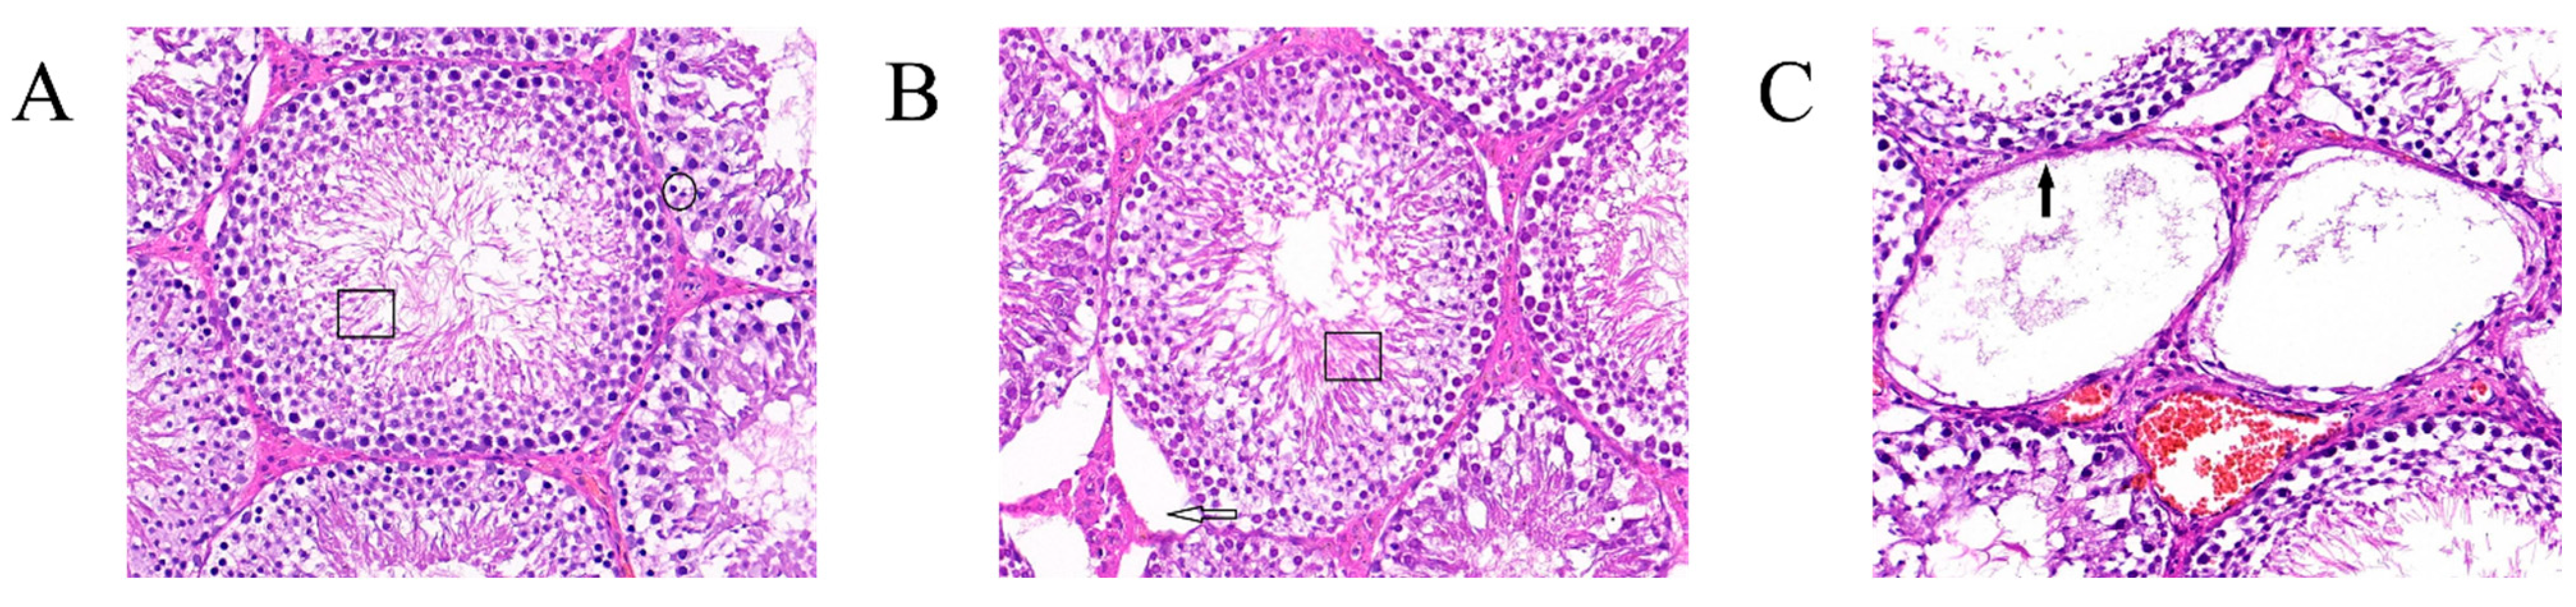

2.7. Changes in the Weight of Rat Testes and Observations of Tissue Sections